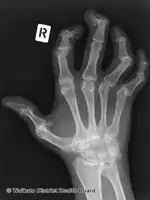

Pain, swelling, or stiffness in one or more joints is commonly present in psoriatic arthritis.[3] Psoriatic arthritis is inflammatory, and affected joints are generally red or warm to the touch.[3] Asymmetrical oligoarthritis, defined as inflammation affecting two to four joints during the first six months of disease, is present in 70% of cases. However, in 15% of cases, the arthritis is symmetrical. The joints of the hand that is involved in psoriasis are the proximal interphalangeal (PIP), the distal interphalangeal (DIP), the metacarpophalangeal (MCP), and the wrist. Involvement of the distal interphalangeal joints (DIP) is a characteristic feature and is present in 15% of cases.

In addition to affecting the joints of the hands and wrists, psoriatic arthritis may affect the fingers, nails, and skin. Sausage-like swelling in the fingers or toes, known as dactylitis, may occur.[3] Psoriasis can also cause changes to the nails, such as pitting or separation from the nail bed,[3] onycholysis, hyperkeratosis under the nails, and horizontal ridging.[4] Psoriasis classically presents with scaly skin lesions, which are most commonly seen over extensor surfaces such as the scalp, natal cleft and umbilicus.

• Arthritis symptoms in the distal Interphalangeal articulations of hand (the joints closest to the tips of the fingers). This is not typical of rheumatoid arthritis.

• Distal interphalangeal predominant (M07.0): This type of psoriatic arthritis is found in about 5% of patients, and is characterized by inflammation and stiffness in the joints nearest to the ends of the fingers and toes. Nail changes are often marked.